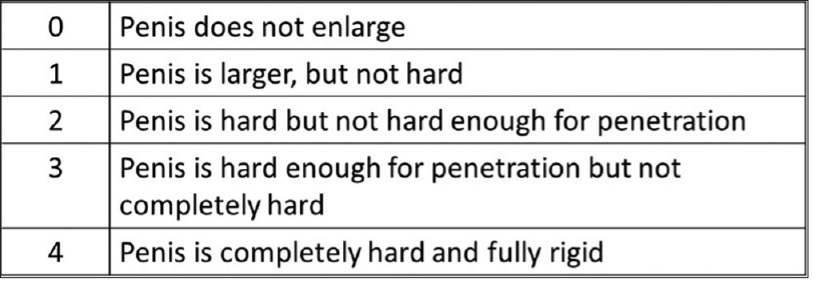

Erection grade was recorded on a scale of 1 to 4 with increments of 0.5 based on the Erection Hardness Score (EHS).

Figure 1 EHS (Goldstein, et al., 2008)

Figure 1 EHS (Goldstein, et al., 2008)